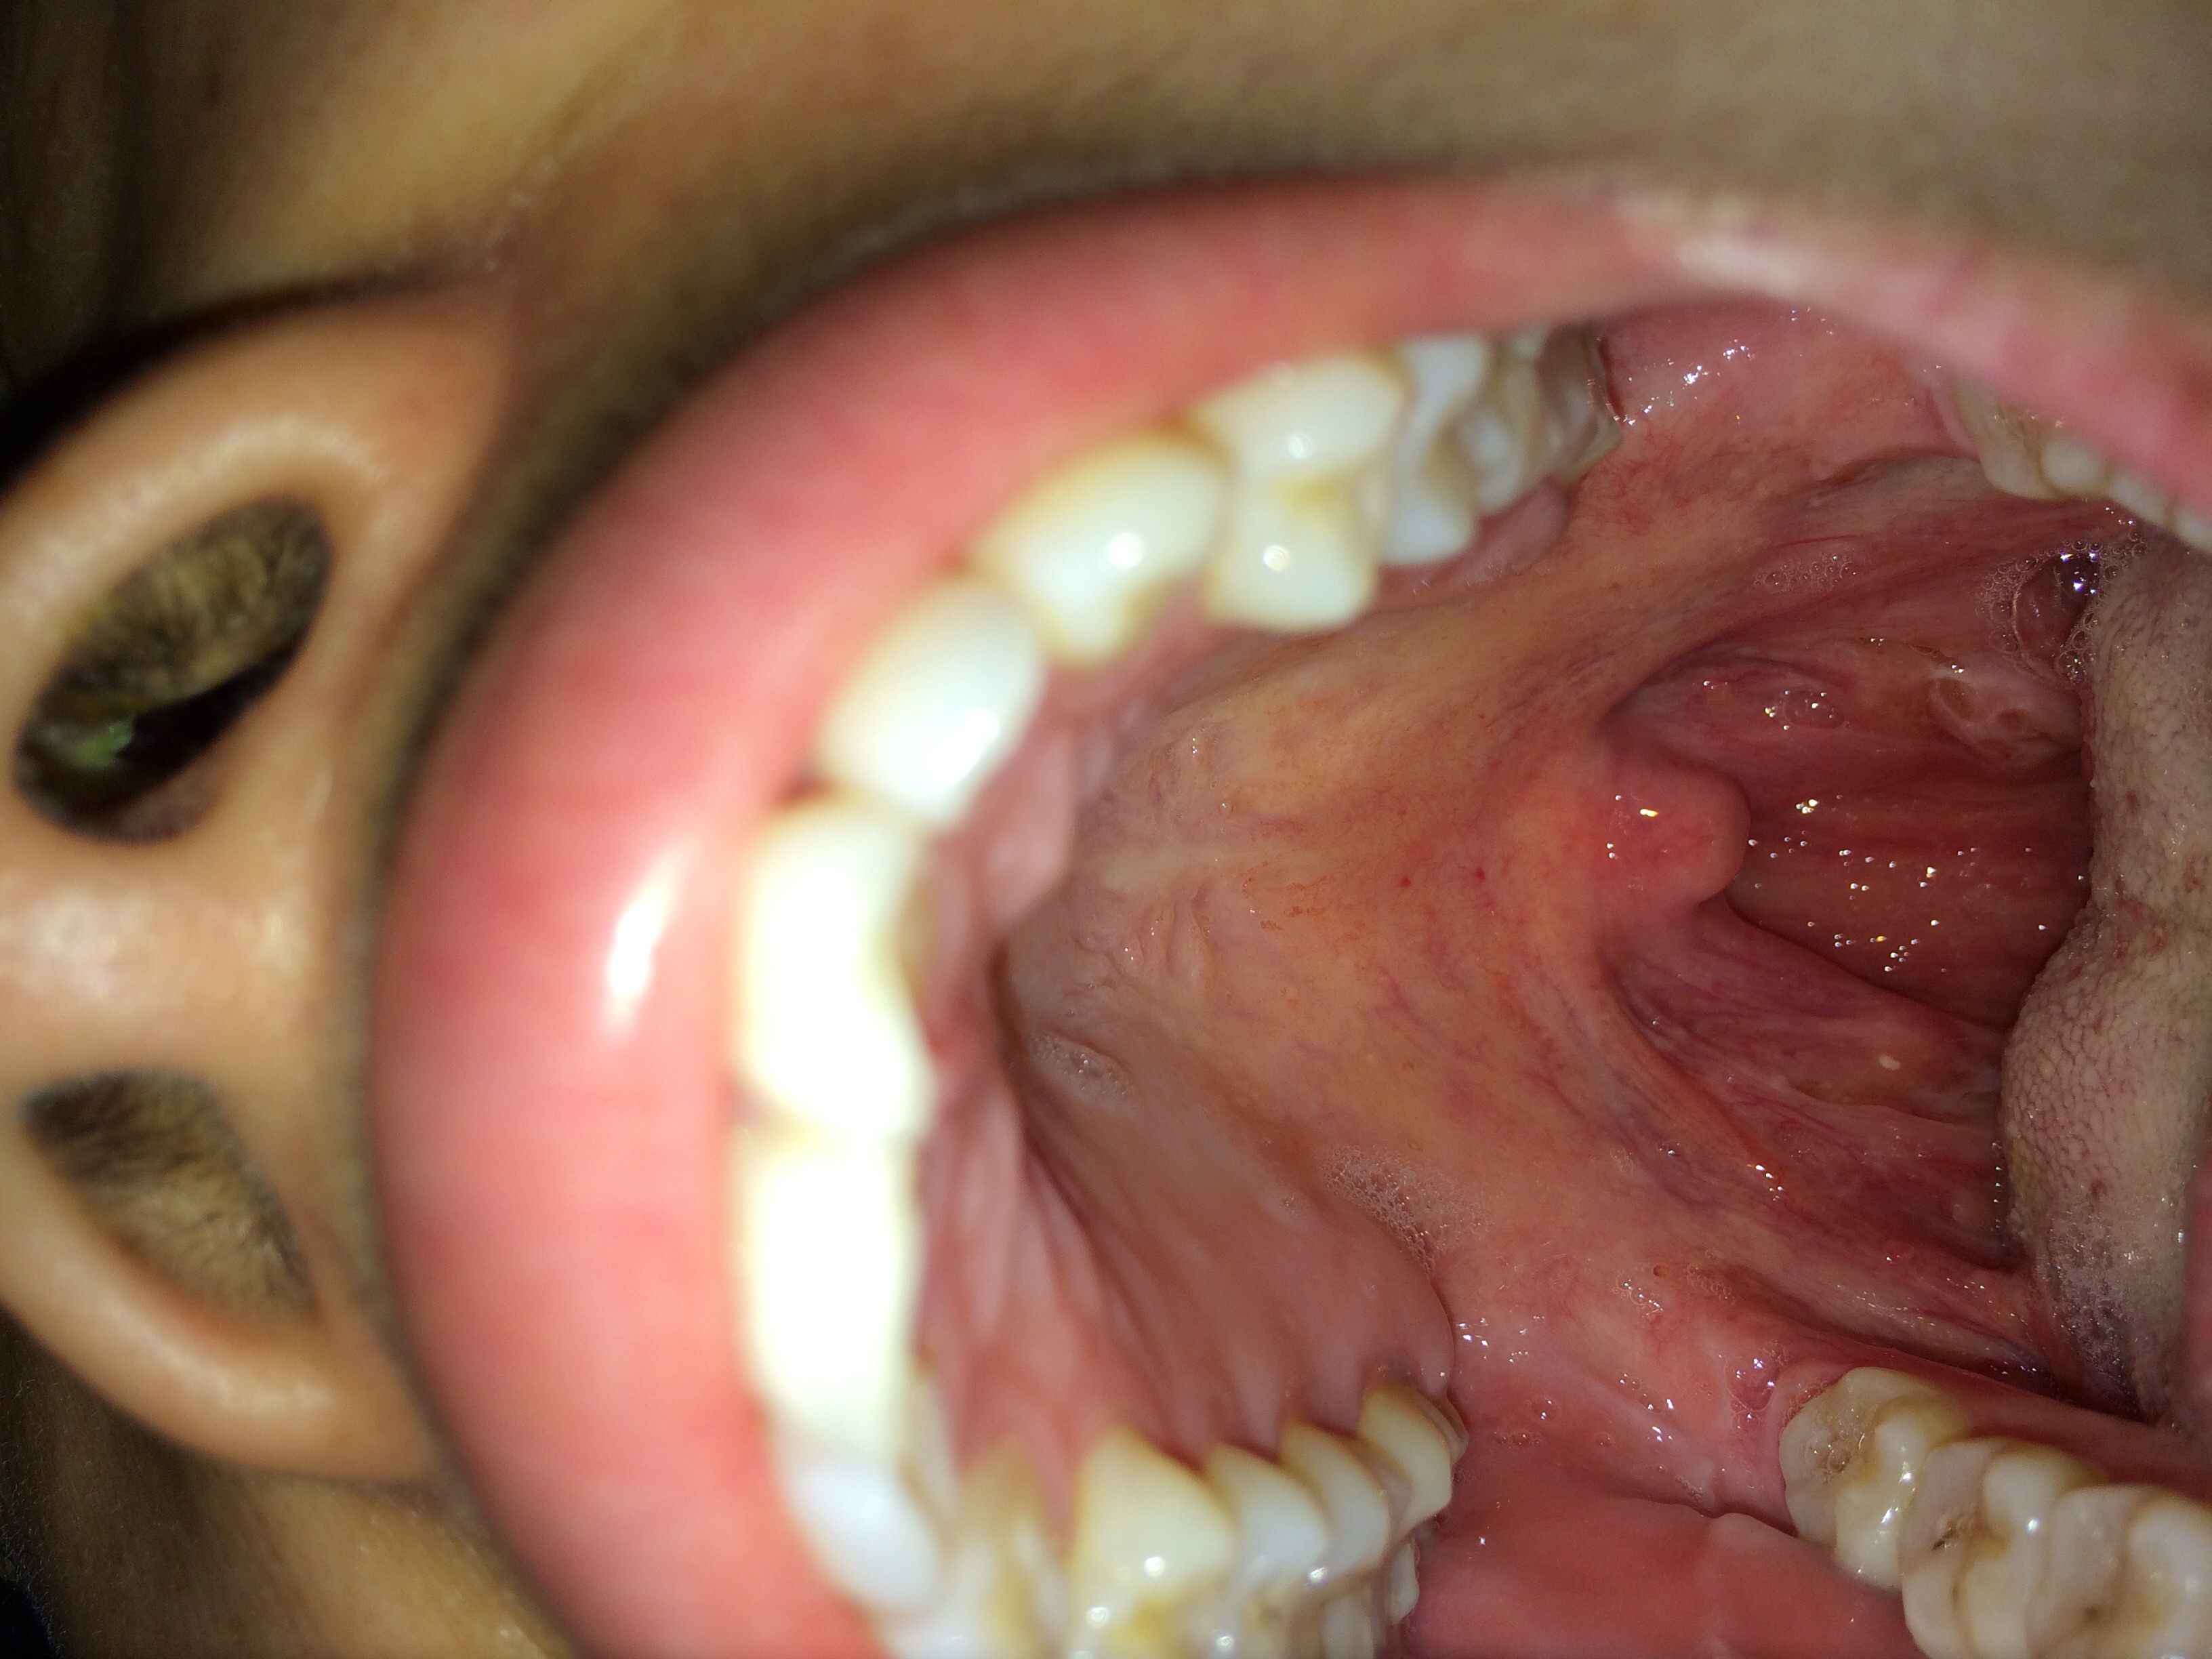

28岁,右侧扁桃体肿大应该吃什么药?没发烧.

慢性扁桃体炎

急性扁桃体炎

右侧化脓性扁桃体炎

请问这属于扁桃体发炎吗?